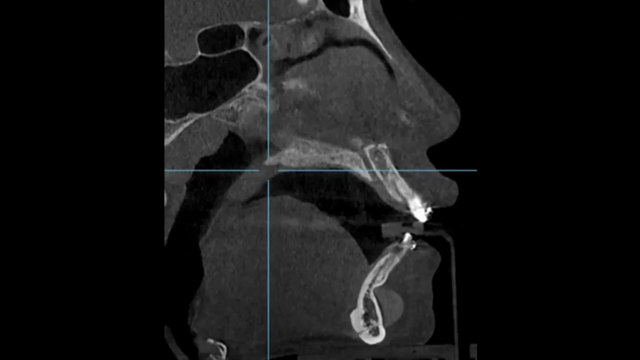

顔面輪郭シリコンプロテーゼ副作用 歯痛 -専門医が直接分析致します 1

顔面輪郭手術後の痛み “顔に針金” -形成外科専門医の原因分析

両顎手術後、ずっと口から膿が出ます -専門医がお教えする副作用と再手術3